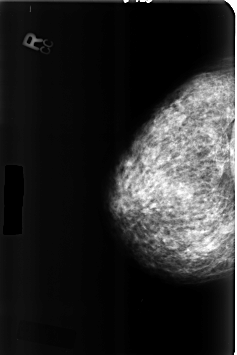

ics_version 1.0 filename B-3357-1 DATE_OF_STUDY 25 7 1995 PATIENT_AGE 55 FILM FILM_TYPE REGULAR DENSITY 3 DATE_DIGITIZED 13 7 1998 DIGITIZER LUMISYS LASER SEQUENCE LEFT_CC LINES 4664 PIXELS_PER_LINE 3096 BITS_PER_PIXEL 12 RESOLUTION 50 OVERLAY LEFT_MLO LINES 4640 PIXELS_PER_LINE 3080 BITS_PER_PIXEL 12 RESOLUTION 50 OVERLAY RIGHT_CC LINES 4608 PIXELS_PER_LINE 3072 BITS_PER_PIXEL 12 RESOLUTION 50 NON_OVERLAY RIGHT_MLO LINES 4624 PIXELS_PER_LINE 3096 BITS_PER_PIXEL 12 RESOLUTION 50 NON_OVERLAY |